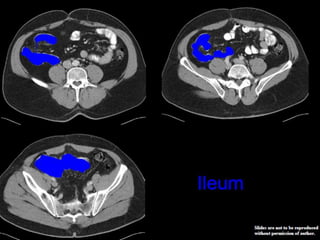

CT cross sectional

anatomy.